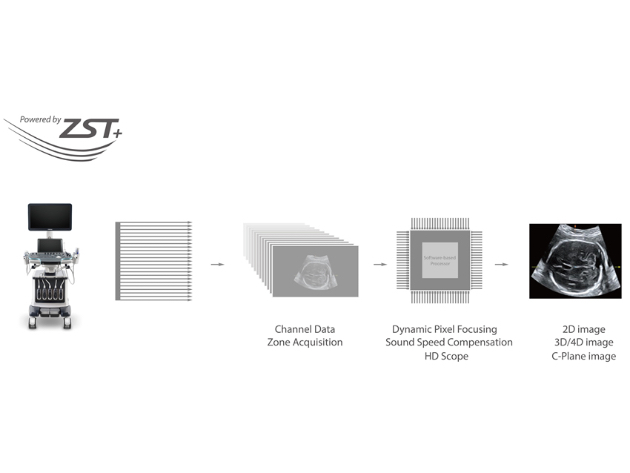

Since the company was founded, Mindray is continuously exploring new ways to improve diagnostic confidence. Powered by the most revolutionary ZONE Sonography? Technology, the ZST+ platform brings ultrasound image quality to a higher level by zone acquisition and channel data processing platform brings ultrasound image quality to a higher level by zone acquisition and channel data processing.

The channel data based ZST+?is an extraordinary innovation, representing an ultrasound evolution. Transforming ultrasound metrics from conventional beamforming to channel data based processing, ZST+?is more powerful and flexible to integrate the latest innovative OB/GYN imaging technologies, and to deliver a higher level of imaging performance in 2D, 3D/4D, and even the coronal plane image.